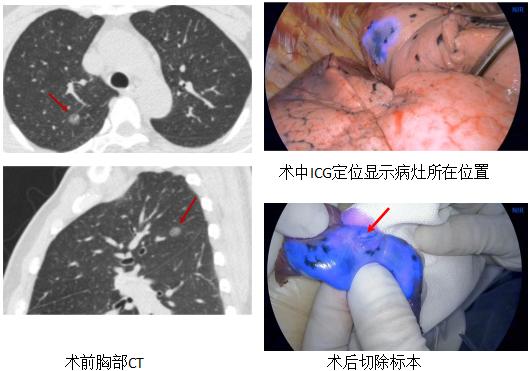

二、支气管镜在周围型肺癌定位中的应用

传统的定位方法都是经皮的,金属勾线、金属线圈、染料标记,但是也可以经支气管镜。

VBN引导下注射亚甲蓝胸腔镜术前肺微小病变定位

ENB引导下注射亚甲蓝联合CT引导Hook-wire胸腔镜术前肺微小病变定位

ENB引导下注射ICG胸腔镜术前肺微小病变定位